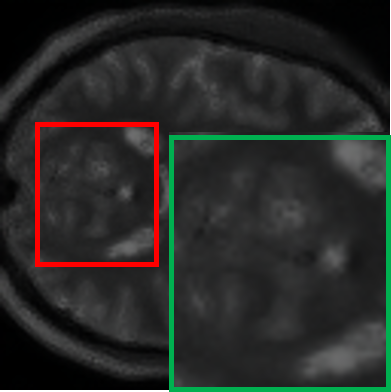

IV-C Selection of the step count for student model

In the progressive distillation framework, the step count N𝑁Nitalic_N represents the total number of steps in the 1.5T-to-7T SR task. Adjusting N𝑁Nitalic_N directly affects the granularity of the student model’s intermediate targets, influencing both the distillation process’s effectiveness and computational complexity. Table III highlights the impact of varying N𝑁Nitalic_N on the distillation framework, visualized in a 3D embedding space using t-SNE [44]. The points include the real 1.5T data (a blue point), the middle-step reconstructed data (small grey points), and the 7T-like output data of the teacher model (a red point). As can be seen, as N𝑁Nitalic_N increases, the student model benefits from more intermediate subgoals, enabling finer-grained guidance for resolution refinement. Specifically, for N<20𝑁20N<20italic_N < 20, the limited intermediate steps force the student model to make abrupt, large transitions, leading to difficulty in denoising and refining structural details. Conversely, increasing N𝑁Nitalic_N to 50 smoothens the refinement trajectory, allowing for smaller incremental changes and better structural preservation. This trend is quantified by the decreasing PS percentage differences shown below each plot. As can be seen, for N=20𝑁20N=20italic_N = 20, the student model achieves around 90%percent\%% of the teacher model’s performance in PSNR. The computational and inference cost associated with higher N𝑁Nitalic_N becomes substantial, and the minor improvements in quality no longer justify the added overhead. It is noteworthy that the computational complexity of the distillation process is not solely linear with respect to N𝑁Nitalic_N, it is also significantly influenced by the structural design of the student model. In theory, increasing N𝑁Nitalic_N could be balanced by employing a lighter student model, as the reduced per-step computational demands would offset the increase in the number of refinement steps. However, extensive experimentation in our study revealed that overly lightweight student models face substantial limitations in their denoising capabilities. Specifically, even with larger N𝑁Nitalic_N values, such models struggle to refine noised latent representations into high-quality outputs, which arises from their inability to capture complex structural details and high-frequency information. Considering these factors, N=20𝑁20N=20italic_N = 20 emerges as the practical choice for this study. This configuration strikes a balance between sufficient refinement stages and computational efficiency, ensuring that the student model has enough capacity to handle the intermediate targets while avoiding diminishing returns and excessive costs associated with larger N𝑁Nitalic_N values.

TABLE III: Visualization of student model paths under different step counts N𝑁Nitalic_N

N𝑁Nitalic_N=5 N𝑁Nitalic_N=10 N𝑁Nitalic_N=20 N𝑁Nitalic_N=30 N𝑁Nitalic_N=50

[Uncaptioned image] [Uncaptioned image] [Uncaptioned image] [Uncaptioned image] [Uncaptioned image]

PSNR: 6.29 (86%\%\downarrow% ↓) PSNR: 18.31 (59%\%\downarrow% ↓) PSNR: 39.03 (13%\%\downarrow% ↓) PSNR: 39.88 (12%\%\downarrow% ↓) PSNR: 40.36 (11%\%\downarrow% ↓)

• *

According to the Fig. 4, the average PSNR of 45.11 (dB) is as the teacher reference.

As shown in Table IV, the student model demonstrates a significant reduction in computational complexity and parameter count compared to the teacher model. Specifically, the student model achieves a 59%percent\%% reduction in FLOPs and a 69%percent\%% reduction in parameter number, underscoring its efficiency. Despite this substantial reduction, the student model retains competitive performance, with only a 13%percent\%% decrease in PSNR (from 45.11dB to 39.03dB) and a 6%percent\%% decrease in SSIM (from 0.96 to 0.90), which demonstrates the effectiveness of the student model in maintaining high-quality super-resolution results while significantly reducing resource requirements. Moreover, these results reflect the effectiveness of the progressive distillation framework, making it more suitable for deployment in resource-constrained environments.